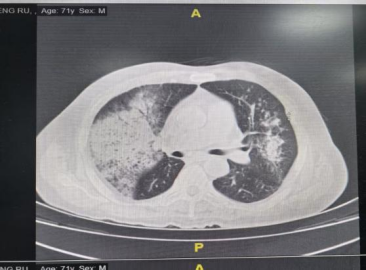

胸部CT:双肺炎症。

11月10日: